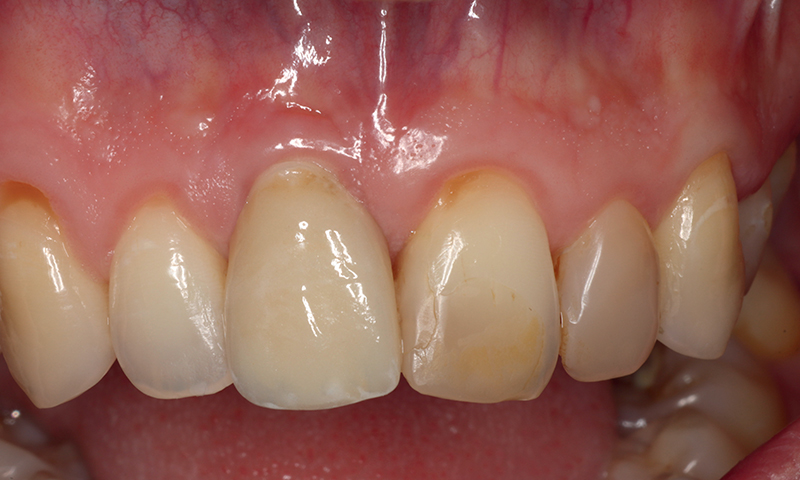

Fig. 10 (caso 2) - Vista frontale dopo 3 mesi dall'inserimento dell'impianto

Caso 2: Una paziente di 33 anni si presentava con corona clinica del dente 11 scolorita, associata ad una linea del sorriso alta, che rappresentava una sfida per il risultato estetico. Il dente era associato a riassorbimento apicale, cisti e sintomi dolorosi. Veniva estratto e la paziente riceveva un impianto SDS. L'intervento seguiva scrupolosamente il protocollo di perforazione ossea suggerito dal produttore, e l'intervento mini-invasivo manteneva intatte la parete buccale dell'alveolo dentale. La competenza del chirurgo si rivelava fondamentale per ottenere un risultato estetico favorevole, fin dai primi passi. Lo spazio tra l'impianto e la parete vestibolare (circa 0,5-1 mm) veniva riempito con matrici PRF, per stimolare la formazione di nuovo osso. In questo caso non era necessaria la sutura. Dopo 3 mesi l’impianto era preparato e la paziente riceveva la corona definitiva. La paziente era soddisfatta del trattamento (Fig. 3-10).